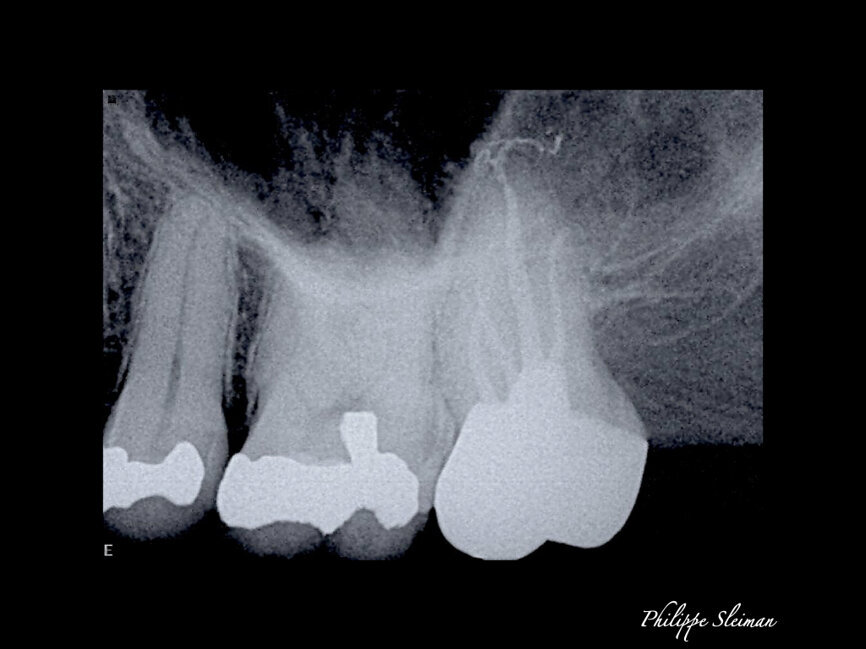

For shaping, you need to start, after establishing a glide path, with 21 mm stainless-steel hand files. I use a 17 mm orifice opener because it allows me to work way in the back with indirect vision, and this step will shape the first part of the canal, making it easy for the remaining rotary files to follow the path that has been created. The final radiographs revealed four separate root canals (Fig. 3). Figure 4, a micro-CT scan done by Dr Volokitin, shows almost the same anatomy.

The patient was referred for a root canal therapy of his maxillary molar. Upon creating the access cavity under a clinical microscope, we could see that the entry to the second mesial canal was at a distance from the entrance to the first (Fig. 5). Figure 6 shows the proximity of the second mesiobuccal canal to the palatal canal. Increasingly, second mesial canals are being treated in the maxillary second molar owing to the use of the microscope, ultrasonic instruments and irrigation and of course owing to the clinical knowledge regarding the use of these and owing to the use of CBCT imaging sometimes.

Figure 7 shows an immediate postoperative radiograph of the treatment. A micro-CT scan of a similar root canal system is shown in Figure 8.